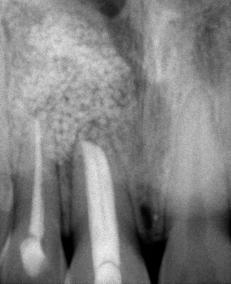

Terapéutica endoquirúrgica para periodontitis apical crónica: reporte de un caso

Tratamiento

Investigación clínica

Figura 2. Fotografías oclusales y ortopantomografía. A. Vista de la arcada superior. B. Vista de la arcada inferior. C. Ortopantomografía.

dentales en casos de incisivos muy protruidos.18 Los resultados en cierta parte dependerán de la colaboración en el uso del AOF, y del diseño y confección adecuados del mismo.19 El tratamiento en una fase temprana podrá prevenir disgnacias esqueléticas y dentarias.20 Al estimular el desarrollo o actuar sobre las suturas cuando son permeables a estímulos biomecánicos y funcionales buscando reducir la posibilidad de una cirugía ortognática; reducir el tiempo y la complejidad de tratamientos correctivos ortodóncicos de segunda fase.21

En 2004, Simoes propone el uso de aparatos funcionales, los Simoes Network (SN), diseñados para el tratamiento de diferentes maloclusiones en sintonía con los picos de crecimiento.22 Dentro de la ortopedia funcional de los maxilares, existen principios fundamentales como los cambios de postura terapéuticos y la excitación neural, los cuales se cumplen en los aparatos funcionales

como Bimler, Bionator, Frankel, Planas y los SN.23 El SN1 se caracteriza por llevar dentro de su estructura, arco vestibular, resortes frontales, tubo telescópico inferior, arcos de conducción inferior mandibular, tornillos de expansión.24

Los músculos, como si fueran cordones, controlan las posiciones solicitadas cuando la boca se cierra con AOF. El sistema sensorial y el sistema motor alteran la posición de la lengua y los dientes. Por lo tanto, se educan o reeducan y el sistema neural desarrolla reflejos posturales y de movimiento para mantener la armonía entre ATM y arcos dentarios.25 El esqueleto de acero, protege y apoya las arcadas dentarias por dentro y por fuera y trasmite directamente las fuerzas inducidas por reflejo en los músculos circundantes hasta las superficies de los dientes, conduciéndolas hasta los lugares de mayor equilibrio individual.26

Pedro Planas realizó aparatos para la liberación total o parcial de los movimientos mandibulares. Estos aparatos impiden recidivas porque nos dan libertad de movimientos y eliminan interferencias para llegar a los ángulos funcionales masticatorios iguales, los cuales fueron equilibrados por pistas artificiales (pistas planas), con el nombre de pistas indirectas planas simples (PIPS).27 Las almohadillas vestibulares se utilizan como auxiliar en el tratamiento sin extracciones, este es un aparato con acción ortopédica para aumentar el perímetro del arco tanto mandibular como del maxilar, aliviando también la presión de los labios y carrillos.28 El equiplan funciona como un equilibrador del plano oclusal, este actúa a base de estímulos que inducen modificaciones dentarias y óseas, mediante una

nueva información al sistema sensorial.29

El objetivo de analizar estos conceptos es presentar un caso clínico de paciente masculino de 10 años, clase II división 2, con mordida profunda empleando aparatología ortopédica de Simoes Network y de Pistas Planas.

Reporte de caso clínico

Paciente masculino de 10 años, se presenta a la consulta en la clínica Gnathos, la mamá reporta desagrado en la estética dental y facial del paciente. En la exploración clínica se observa mordida profunda, amplio número de piezas dentales con caries, fracturas dentales, mala higiene y encías inflamadas. presenta clase II división 2, se le indicaron estudios complementarios para diagnóstico asertivo, modelos de estudio,

Tratamiento de mordida profunda

radiografía panorámica y lateral de cráneo, fotografía intraoral y extraoral, historia clínica y consentimiento informado.

Metodología

Después de haber realizado el diagnóstico y plan de tratamiento, se remitió a extracción de restos

Figura 3. Primer aparto SN1 con almohadillas vestibulares. A. VF con aparato, B. VL derecha C. VL izquierda. D. SN1, vista oclusal (VO). Después de 7 meses del tratamiento se observa los avances obtenidos por el aparato y los ajustes del mismo los cuales observamos en las figuras: E. VO del SN1 7mm de crecimiento transversal, F. VF con aparato, 3G. VL derecha, H. VL izquierda.

Figura 4. Segundo Aparato SN1. A. VF con aparato, B. VL derecha, C. VL izquierda, 3D. SN1, VO. Después de 5 meses del tratamiento se observa los avances obtenidos por el aparato y los ajustes del mismo los cuales observamos en la imagen, E. VO del SN1 5 mm de crecimiento transversal, F. VF con aparato, G. VL derecha, H. VL izquierda.

Figura 5. Tercer aparato PIPS A. VF con aparato, B. VL derecha, C. VL izquierda, D. PIPS VO. Después de 7 meses del tratamiento se observa los avances obtenidos por el aparato y los ajustes del mismo los cuales observamos en la imagen, E. VO del PIPS sin los mantenedores de espacio, 5. VF con aparato, 5G. VL derecha, 5H. VL izquierda.

radiculares de O.D. 73 y 83 y rehabilitación oral completa de O.D. 54, 63,65 y 75. Se procedió a colocar aparatos ortopédicos para corrección de la maloclusión en enero del 2022.

El tratamiento inicio con AOF, SN1 con Equiplan adicionando almohadillas vestibulares en el maxilar para despresurizar la acción de la musculatura labial. La indicación de uso fue utilizarlo de forma continua solo retirándose para comer e higienizar, activar del tornillo tanto superior como inferior una vez a la semana, y se realizaron revisiones mensuales en la clínica para valorar avances, llevar

a cabo activaciones, ajustes del aparato e indicaciones. Como se observa en la Figura 3.

Al haber obtenido los avances programados en la corrección de la sobremordida vertical con esté AOF, se decide cambiar a un nuevo SN1, con equiplan sin almohadillas y con arco vestibular esto para continuar regularizando el plano de oclusión en el paciente, y fue utilizado por 5 meses de forma continua. Se mantuvieron las mismas indicaciones de uso, que en el aparato anterior. Como podemos observar en la Figura 4

El AOF Sn1 logró el avance mandibular, expansión programada, armonización de arcadas y regularización de la curva de Spee, entonces se determina cambiar dicho aparato por unas PIPS, clase I para mantener el espacio que corresponde a los O.D. 35 y 45, ya que fueron indicadas para extracción los O.D. 75 y 85, esperando la erupción de premolares para terminar el anclaje. Las indicaciones para el paciente fueron uso continuo de las PIPS por 3 meses, solo retirándose para comer e higienizar, revisiones mensuales en la clínica para activación y desgastes de los mantenedores de espacio, vigilando la erupción de los premolares. Posteriormente se indicó su uso nocturno por 4 meses más para mantener estabilidad de los resultados obtenidos.

Después de 18 meses de tratamiento con ortopedia funcional de los maxilares, podemos hacer una comparativa de los resultados obtenidos.

Discusión

Es fundamental identificar las regiones anatómicas afectadas para sugerir así un adecuado plan de

tratamiento teniendo en cuenta el factor etiológico. 12 Nos facilitó el tratamiento el haber elegido las primeras zonas anatómicas en las cuales queremos ver un cambio de esta manera se llegó a la aparatología de SN1, para lograr una propulsión mandibular, y una rotación craneal del maxilar, al elegir el Equiplan en el aparato lo cual contribuyó a tratar la mordida profunda.

El tratamiento ortopédico debe iniciarse en la dentición primaria o mixta temprana, para evitar que la maloclusión avance, produciendo deformaciones faciales, mejorando la autoestima del paciente y reduciendo el riesgo de traumatismos dentales en casos de incisivos muy protruidos.18 En el caso que reportamos se inició el tratamiento en dentición mixta tardía, corregimos la maloclusión y se comenzó a reducir el problema conforme avanzaba satisfactoriamente el tratamiento con los AOF.

Los resultados en cierta parte dependerán de la colaboración en el uso del AOF, del diseño y confección adecuada del mismo.19

El paciente al utilizarlo se observaron cambios rápidos y continuos, ya que su tratamiento duro 18 meses. Se utilizaron 3 AOF cada uno con diferente diseño para lograr los objetivos fijados en cada etapa.

Una fase temprana podrá prevenir disgnacias esqueléticas y dentarias.20

Al observar las imágenes en el antes y el después podemos concluir que se previenen y se bloquea el avance de la maloclusión dental y esquelética clase II división 2 en el paciente, de esta manera se previenen tratamientos más invasivos y complejos

en un futuro, al hacer uso constante del AOF.

Conclusión

Las maloclusiones se presentan en dentición primaria y mixta, por lo cual es importante empezar su tratamiento temprano durante un periodo de crecimiento del paciente, para estimular el desarrollo esquelético y dental adecuado, corregir e interceptar las maloclusiones, logrando una mayor estabilidad en los tratamientos concluidos y reducir tratamientos quirúrgicos, o proporcionar una base ósea adecuada para que los tratamientos ortodóncicos futuros sean más rápidos. También ayuda en la estética facial del paciente, mejorando su desarrollo psicosocial.

De acuerdo a los autores que reportan la función de los AOF y a los resultados obtenidos con nuestro paciente, llegamos a la conclusión, de que es indispensable un diagnóstico correcto para proyectar un plan

Figura 6. Fotos intraorales antes y después del tratamiento. A. VF B. VL derecha, C. VL izquierda, después de 18 meses de tratamiento D. VF, E. VL derecha, F. VL izquierda.